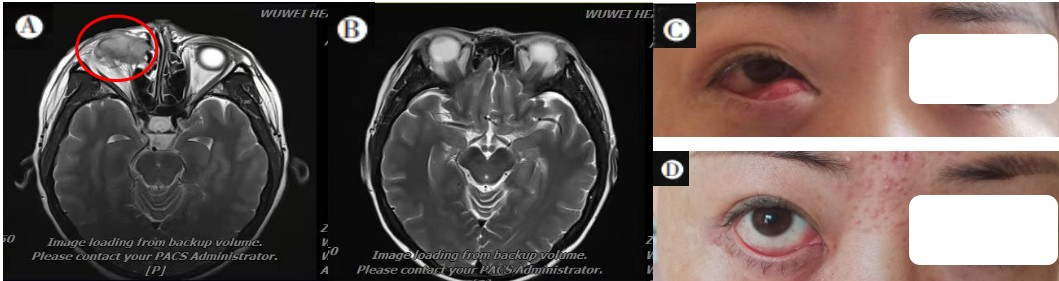

Note A: MRI examination before carbon ion therapy showed: a mass occupying the right lacrimal sac area, invading the eyeball, medial rectus muscle, inferior rectus muscle, and right nasolacrimal duct. The eyeball was compressed and slightly displaced upward; the red circle indicates the range of tumor invasion.B: MRI examination after carbon ion therapy showed complete disappearance of the lesion, with the treatment effect evaluated as complete remission.C: Clinical signs before carbon ion therapy; D: Changes in clinical signs after carbon ion therapy.

Figure 2: Comparison of MRI and Clinical Signs Before and After Carbon Ion Therapy for a Patient with Lacrimal Sac Squamous Cell Carcinoma (Case 1)

On July 9, 2022, an orbital MRI showed:

- A space-occupying lesion in the right lacrimal sac area, invading the eyeball, extraocular muscles, and nasolacrimal duct.

- The eyeball was compressed and slightly displaced upward.

- Local bone destruction was observed in the medial wall, floor of the right orbit, ethmoid sinus, and maxillary sinus.

- The mass locally protruded into the ethmoid sinus and nasal cavity.

During the treatment period, only Grade 1 radiation-induced conjunctival injury occurred, and no late adverse reactions grade 2 or higher were observed.